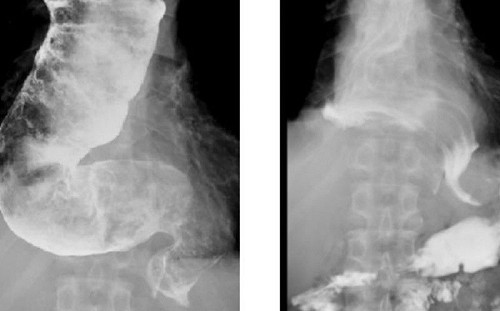

胃食道逆流、胸痛、體重狂降?小心是「食道遲緩不能症」